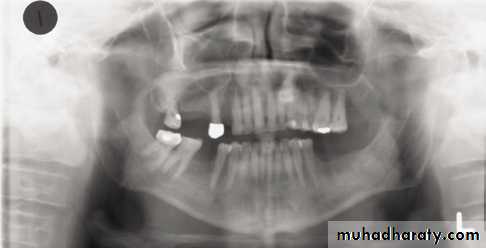

Patient is biting too far back

on rod or not at all

Anterior teeth blurry and wide,

ghosting of mandible and spine,

condyles close to edge of image

Patient too far back; note ghosting of mandible and spine, condyles pushed to outside of film, blurring and widening of anterior teeth